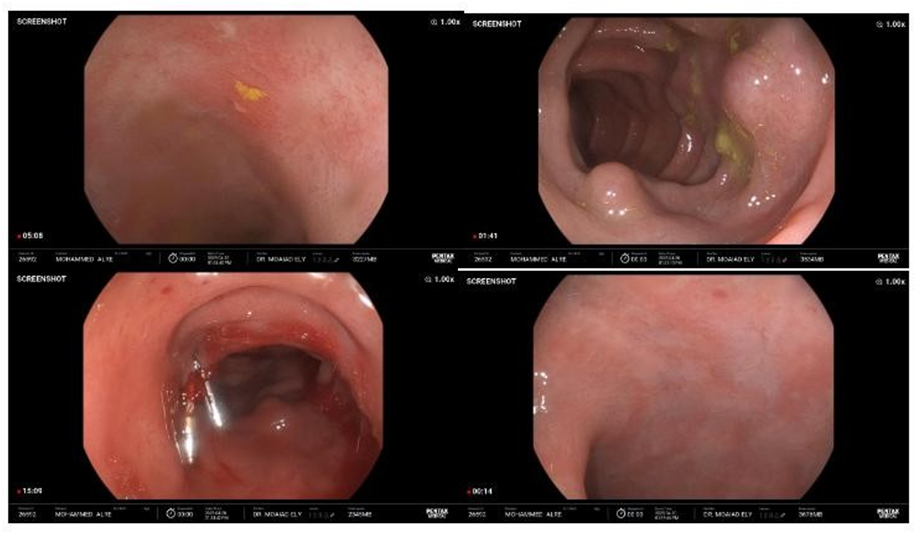

· Colonoscopy:

- Ulceration and inflammation noted in the terminal ileum

- Inflamed rectal mucosa

- A small polyp in the left colon; biopsy resulted in active spurting hemorrhage, suggesting underlying varices

· CT Angiography:

- Dilated colonic veins in the right colon

- No evidence of splenomegaly, portal vein thrombosis, or liver cirrhosis

· Doppler Ultrasound of the Portal Circulation:

- Normal portal vein flow

- No sonographic signs of portal hypertension

The Varices at left side and descending colon, Biopsied small polyp – active spurting bleeding >> small varices